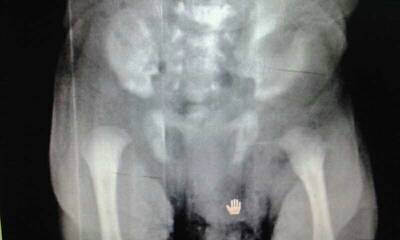

宝宝半个月 左脚老弯着,没有右脚好动,去拍片,医生说是看不出什么 请你们瞧瞧!会是髋关节脱位吗?? 点击展开 32069yahoo 2013-12-03 17:14 为您推荐: 其他回答 病情分析: 你好;按你的检查结果是正常的,考虑是缺钙引起的, 指导意见: 建议积极进行检查确定具体的情况为好。在必要的时候可以用首先补充维生素D或钙质。 赫亦凝_2Vv0 2013-12-03 17:36 相关问题 宝宝左右腿长短不一,右腿长点,站立时左脚向前,右脚有点像右歪是怎么回事?是髋关节脱位么 怀孕12+周两只脚弯痛了两天,左脚弯痛肿了一走路就有点痛,右脚弯没那么痛,这是缺钙,还是脚肿了? 最近右脚弯不下去,今晚发现膝盖外侧处比左脚肿,但是不痛,就是蹲的时候弯不下去,知道怎么回事吗